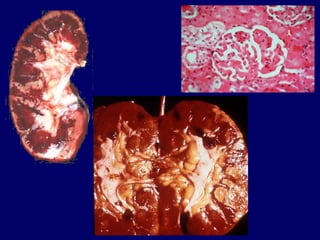

Necrosi Corticale Acuta Grave Insufficienza Renale Acuta Organica caratterizzata da: 1) 2) 2% di tutte le Insufficienze Renali Acute Necrosi ischemica della corticale renale  (glomeruli e vasi arteriosi)  Oligoanuria, prolungata e talora irreversibile

Necrosi Corticale Acuta Gravidanza (distacco precoce di placenta,  emorragia post-partum, aborto settico) Rigetto iperacuto nel Trapianto Renale Crisi emolitiche, Sindrome Emolitico-Uremica Gastroenteriti acute in età pediatrica Pancreatiti Infezioni (Sepsi da batteri GRAM negativi) • • • • • • Etiologia

Necrosi Corticale Acuta Patogenesi Deposizione di fibrina e formazione di trombi intravascolari alle arteriole, piccole arterie e fino alle arterie di calibro maggiore Necrosi massiva di tutte le strutture componenti il parenchima della corticale renale Attivazione del sistema coagulativo (esempio: tromboplastina placentare in corso di gravidanza) • • • • Ischemia prolungata con ipoperfusione della corticale

Necrosi Corticale Acuta: Clinica Insorgenza improvvisa Oligoanuria marcata o anuria (1 – 6 mesi) • • Sindrome uremica acuta a rapida insorgenza  • Quadro clinico - Infezioni - Complicanze cardiache - Complicanze neurologiche - Complicanze gastrointestinali - Alterazioni ematologiche • Coagulazione intravascolare disseminata (CID): • - Trombocitopenia - Ipofibrinogenemia - Consumo di Antitrombina III - Aumento dei prodotti di degradazione della fibrina

Necrosi Corticale Acuta Diagnosi Prognosi • • Terapia • Quadro clinico Ripresa parziale (15%) Insuff. Renale Cronica (80%) Exitus prima della dialisi (90%) Sostitutiva (Dialisi) Medica Specifica